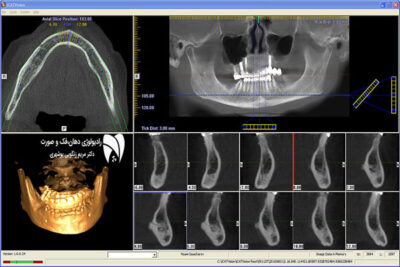

• CBCT

مقایسه CBCT و MCT در دندانپزشکی کشف مزایا و معایب هر روش تصویربرداری و انتخاب بهترین گزینه برای درمان دندان.

مقایسه عملکرد CBCT و MCT با رادیوگرافی متداول

مقایسه CBCT و MCT در دندانپزشکی موضوعی است که در این مطلب، قصد داریم آن را به‌طور جامع برر...

ایمپلنت دیجیتال دندان و مزایای این روش

ایمپلنت دیجیتال دندان: تحول در درمان‌های دندانپزشکی

در این مطلب قصد داریم به موضوع ایمپلنت دیجیتال دندان بپردازیم و نحوه استفاده از فناوری‌های...